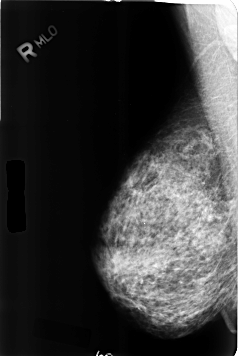

B_3357_1.RIGHT_MLO

RIGHT_CC LINES 4608 PIXELS_PER_LINE 3072 BITS_PER_PIXEL 12 RESOLUTION 50 NON_OVERLAY

RIGHT_MLO LINES 4624 PIXELS_PER_LINE 3096 BITS_PER_PIXEL 12 RESOLUTION 50 NON_OVERLAY